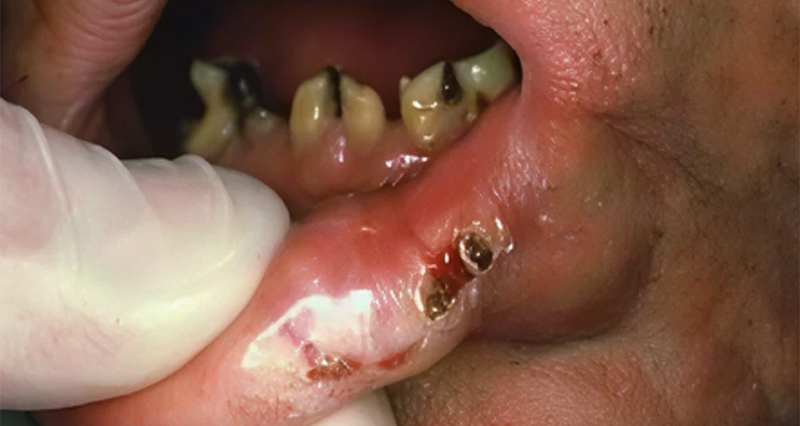

Fig. 01 : cancer du plancher buccal antérieur avec extension à la gencive et à la mandibule.

À côté de ces facteurs, on a également les lésions précancéreuses qui dégénèrent, tel que les leucoplasies, les lichens, les érythroplasies.

L’examen clinique se fera à l’aide d’un bon éclairage. Il sera basé sur l’inspection minutieuse de la cavité buccale, déplissant tous les plis et la recherche d’une seconde localisation, et sur la palpation de la tumeur, de sa périphérie et des chaînes ganglionnaires. Cet examen définira la classification TNM et la forme clinique.